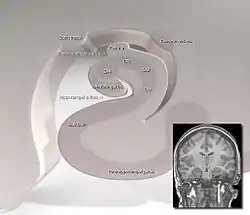

![]() Subiculum to CA1 transition Artist Don Cooper and Leah Leverich | |

The subiculum (Latin for "support") is the most inferior component of the hippocampal formation. It lies between the entorhinal cortex and the CA1 subfield of the hippocampus proper.

The subicular complex comprises a set of related structures including (as well as subiculum proper) prosubiculum, presubiculum, postsubiculum and parasubiculum.[1]

Four component areas have been described:[3] parasubiculum (adjacent to the parahippocampal gyrus), presubiculum, postsubiculum, and prosubiculum.